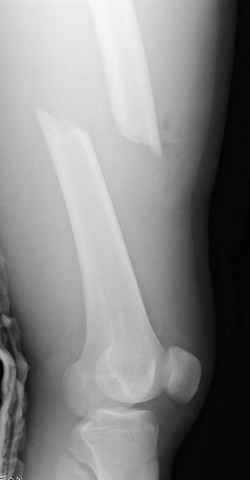

03.14.2005

больному 42, автоавария, политравма, открытая черепномозговая травма, безсознании, открытый перелом бедра, размозжение мягких тканей, дефект кожи на передней поверхности бедра около 13 см2 от ожога, компартмент синдром.

перелом бедра

постоперационные

спасибо за урок, критику принимаю, постараюсь исправится. Уточнения: даты написаны автоматически и надо читать 14-19-24-28 Марта 2005 года, также хирургическая обработка вместе дебрайдмент. (фотографии рентгенограмм скопированы с цифрового ренгенологического архива, извините за качество)